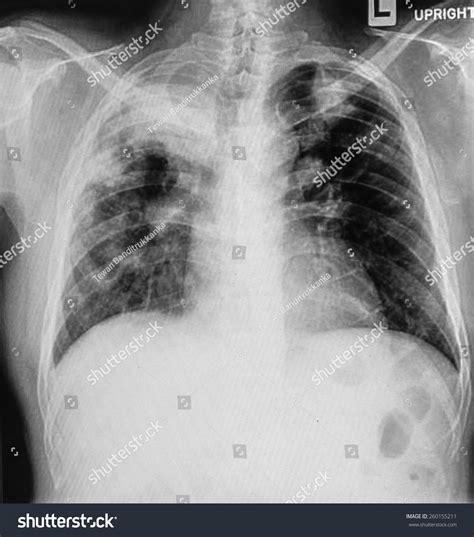

Diagnosing Atelectasis Lung Cancer involves a combination of medical history, physical examination, and diagnostic tests. The diagnostic process typically includes:

• Chest X-ray: An initial imaging test to detect any abnormalities in the lungs.

• CT Scan: A more detailed imaging test that provides a clearer picture of the lung tissue and any potential tumors.